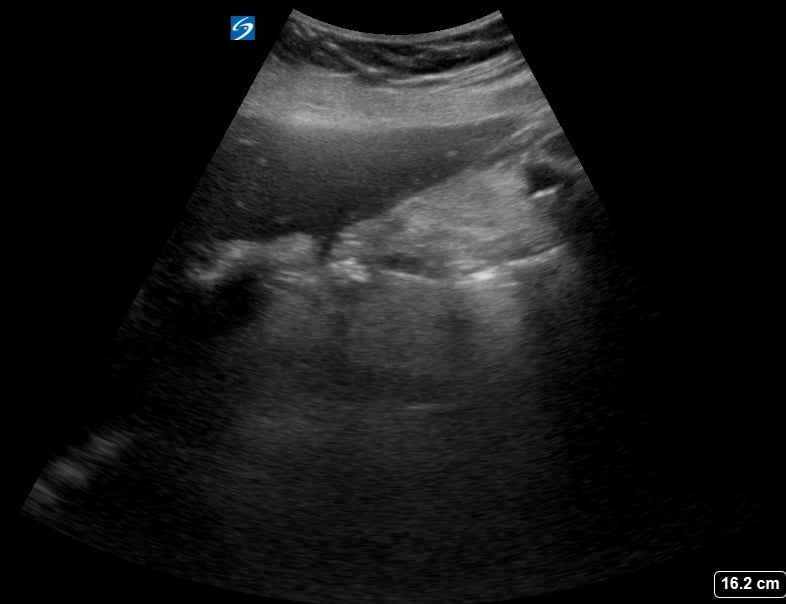

Gallstones are hardened deposits of digestive fluid that can form in the gallbladder, a small organ beneath the liver. In abdominal ultrasound, these concretions appear as hyperechoic structures within the gallbladder lumen, often with posterior acoustic shadowing. Their presence is a common finding during abdominal scans, frequently associated with symptoms like right upper quadrant pain, nausea, and vomiting, particularly after fatty meals.

Medical ultrasound plays a crucial role in diagnosing gallstones and related conditions such as cholecystitis (gallbladder inflammation) or choledocholithiasis (gallstones in the bile duct). Sonographic evaluation helps assess their size, number, and mobility, guiding clinical management and treatment decisions for patients experiencing abdominal discomfort or suspected biliary tract pathology.